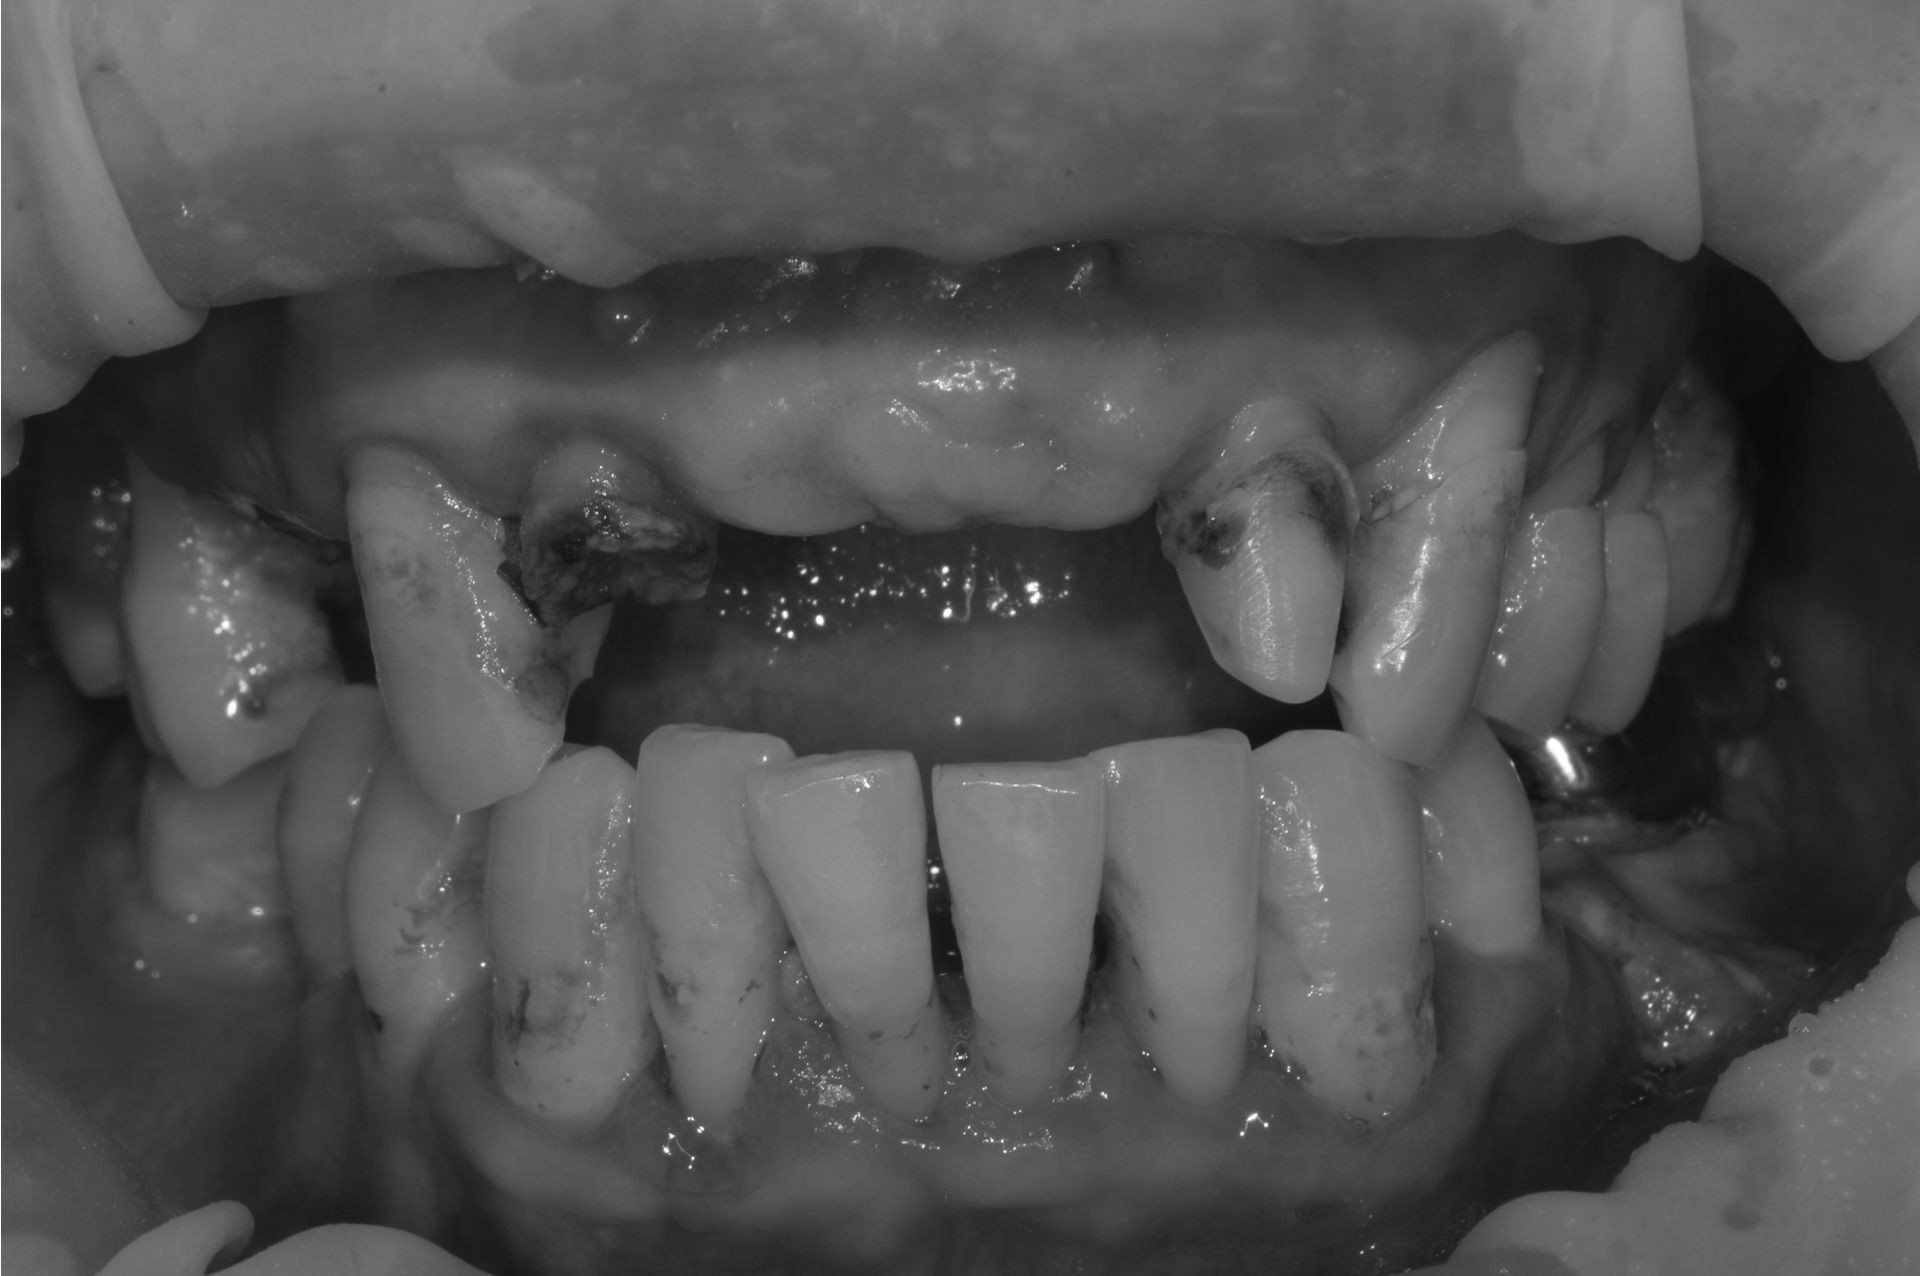

치아우식, 신경치료 및 치은성형술, 심미보철치료

치료 기간 2023. 11. 02 ~ 2023. 12. 20

확장 개원 후 마무리하신 환자분입니다. 앞니 기존 보철물을 하고 계셨지만 치아가 삭아서 보철물이 탈락해서 내원하셨습니다.

환자분께서는 뽑고 임플란트를 생각하고 오셨지만... “치아는 살릴 수 있다면, 살리는 게 좋다.”

간단한 잇몸 수술, 신경치료 후에 기둥을 세워 치아머리만 만들어진다면 충분히 살릴 수 있다고 판단하고 살리는 쪽으로 설명드렸습니다.

환자분들의 치아 하나하나를 소중히 생각하는 참조은치과입니다.

* 상기 사진은 본원 권대근 대표원장이 치료한 환자분의 동의를 받은 이미지 사진으로 실제와 차이가 있을 수 있습니다.